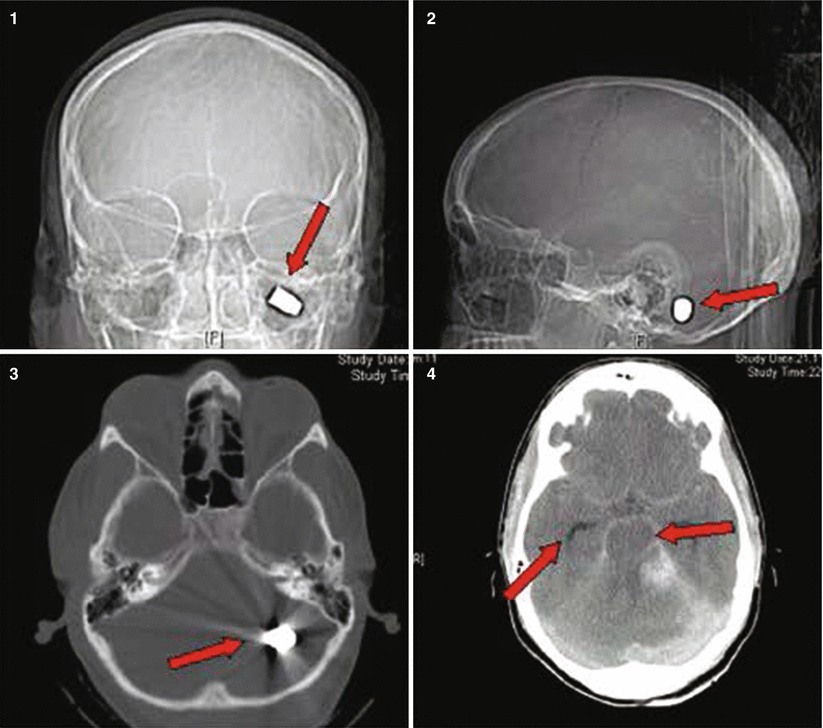

Fig. 27.1

Patient No. 1: a 22-year-old female crime victim, who sustained multiple GSW with a single non-penetrating GSW to the head. Entry wound at R cheek, exit wound on R supraorbital forefront. Plates 1 and 2: scout images A/P and lateral without evidence of bullet. Plates 3 and 4: preoperative images (bone windows) demonstrating R frontal skull fracture with pneumocephalus and orbital roof fracture. Plates 5 and 6: axial and coronal views of large R epidural hematoma and infraorbital hematoma. Plates 7 and 8: axial views of postoperative results status post evacuation of hematoma and autologous cranioplasty. Plates 9 and 10: reconstructed orbital roof status post transfrontal evacuation of retro-orbital hematoma